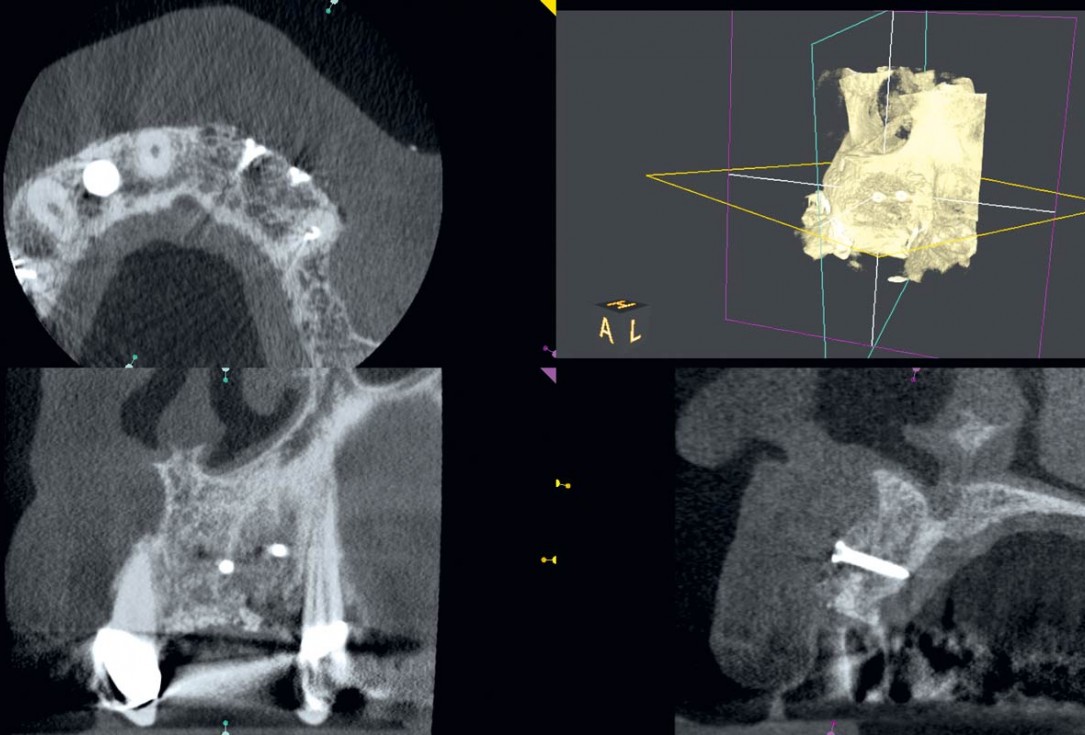

Regeneration of a 9 mm vertical bone defect with cerabone®, autologous bone and S-PRF –  Dr. A. Eslava

Initial x-ray showing bone loss around implants placed 5 years ago in another dental clinic